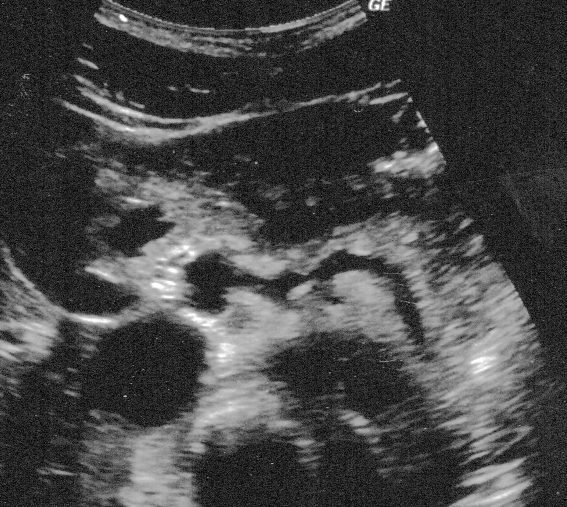

また、超音波ビームの屈折により後方の構造物が二重に表示されることがある。レンズ効果と呼ばれ、屈折が原因で観察されるアーチファクトである。

上の写真では腹腔動脈が2本あるように見えるが、レンズ効果によるアーチファクトである。